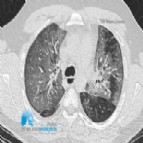

ALTERAÇÕES TOMOGRÁFICAS PERSISTEM 2 ANOS APÓS COVID GRAVE

Dois anos após a hospitalização por COVID-19 grave, mais de um terço de 144 pacientes dos primeiros dias da pandemia apresentava anormalidades pulmonares persistentes em tomografias computadorizadas do t...